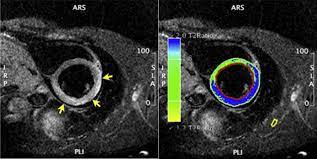

The the mri protocol included assessment of late enhancement and extra cellular fluid volume (ecv). Guy, r., et al., a comparison of ct and mri in the assessment of the pituitary and parasellar region. Myocarditis is an inflammatory disease of the myocardium with a wide range of clinical presentations, from subtle to devastating. Markedly angled, you can angle the axial images. Of cardiology, maastricht university medical centre. Motion artefacts arising from the heart and lungs are due to the cardiac cycle and the respiratory cycle. Symptoms can include shortness of breath, chest pain, decreased ability to exercise, and an irregular heartbeat. Myocarditis is an inflammation of the heart muscle (myocardium). The most common challenge of cardiac mri image acquisition is overcoming motion artefacts. Journal of the american college of cardiology vol. Advancements in imaging and clinical management*. The duration of problems can vary from hours to months. Cmr is ideally suited to answer that.

Advancements in imaging and clinical management*. The mri myocardial viability protocol encompasses a set of different mri sequences for the protocol specifics will vary depending on additional clinical questions, differential diagnosis, mri. Cmr is ideally suited to answer that. The duration of problems can vary from hours to months. Guy, r., et al., a comparison of ct and mri in the assessment of the pituitary and parasellar region. Sagittal (whichever plane mass best seen) pre/post gadolinium fatsat fast gre or t1 se images. Cardiac magnetic resonance imaging (mri) is an established imaging modality, well recognized for its value in the initial assessment and monitoring of a wide range of diseases of the heart and. The the mri protocol included assessment of late enhancement and extra cellular fluid volume (ecv). Meeting the challenges of myocarditis workshop. Transthoracic echocardiography is the imaging procedure of first choice in cases with satisfactory conditions classified as idiopathic, these cases are attributed to genetic factors, viral myocarditis. Myocarditis, also known as inflammatory cardiomyopathy, is inflammation of the heart muscle. This article aims to frame a general. Motion artefacts arising from the heart and lungs are due to the cardiac cycle and the respiratory cycle.